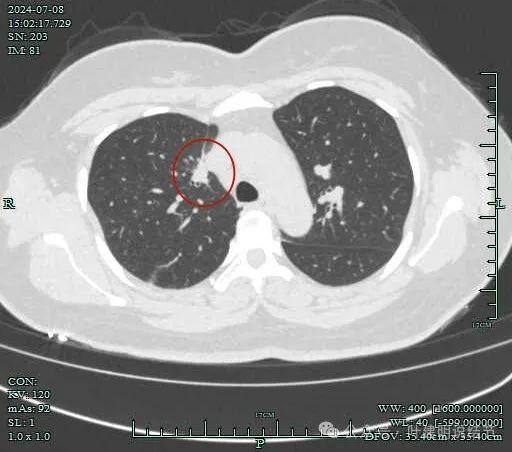

再看2024年7月份的影像:

病灶有毛刺与小棘突征,有邻近细支气管扩张,表面不平,膨胀性不明显。

毛刺征明显,灶边细支气管扩张。

病灶整体轮廓还是较为清楚的。

病灶边支气管可见。

病灶小,但有一定收缩感。